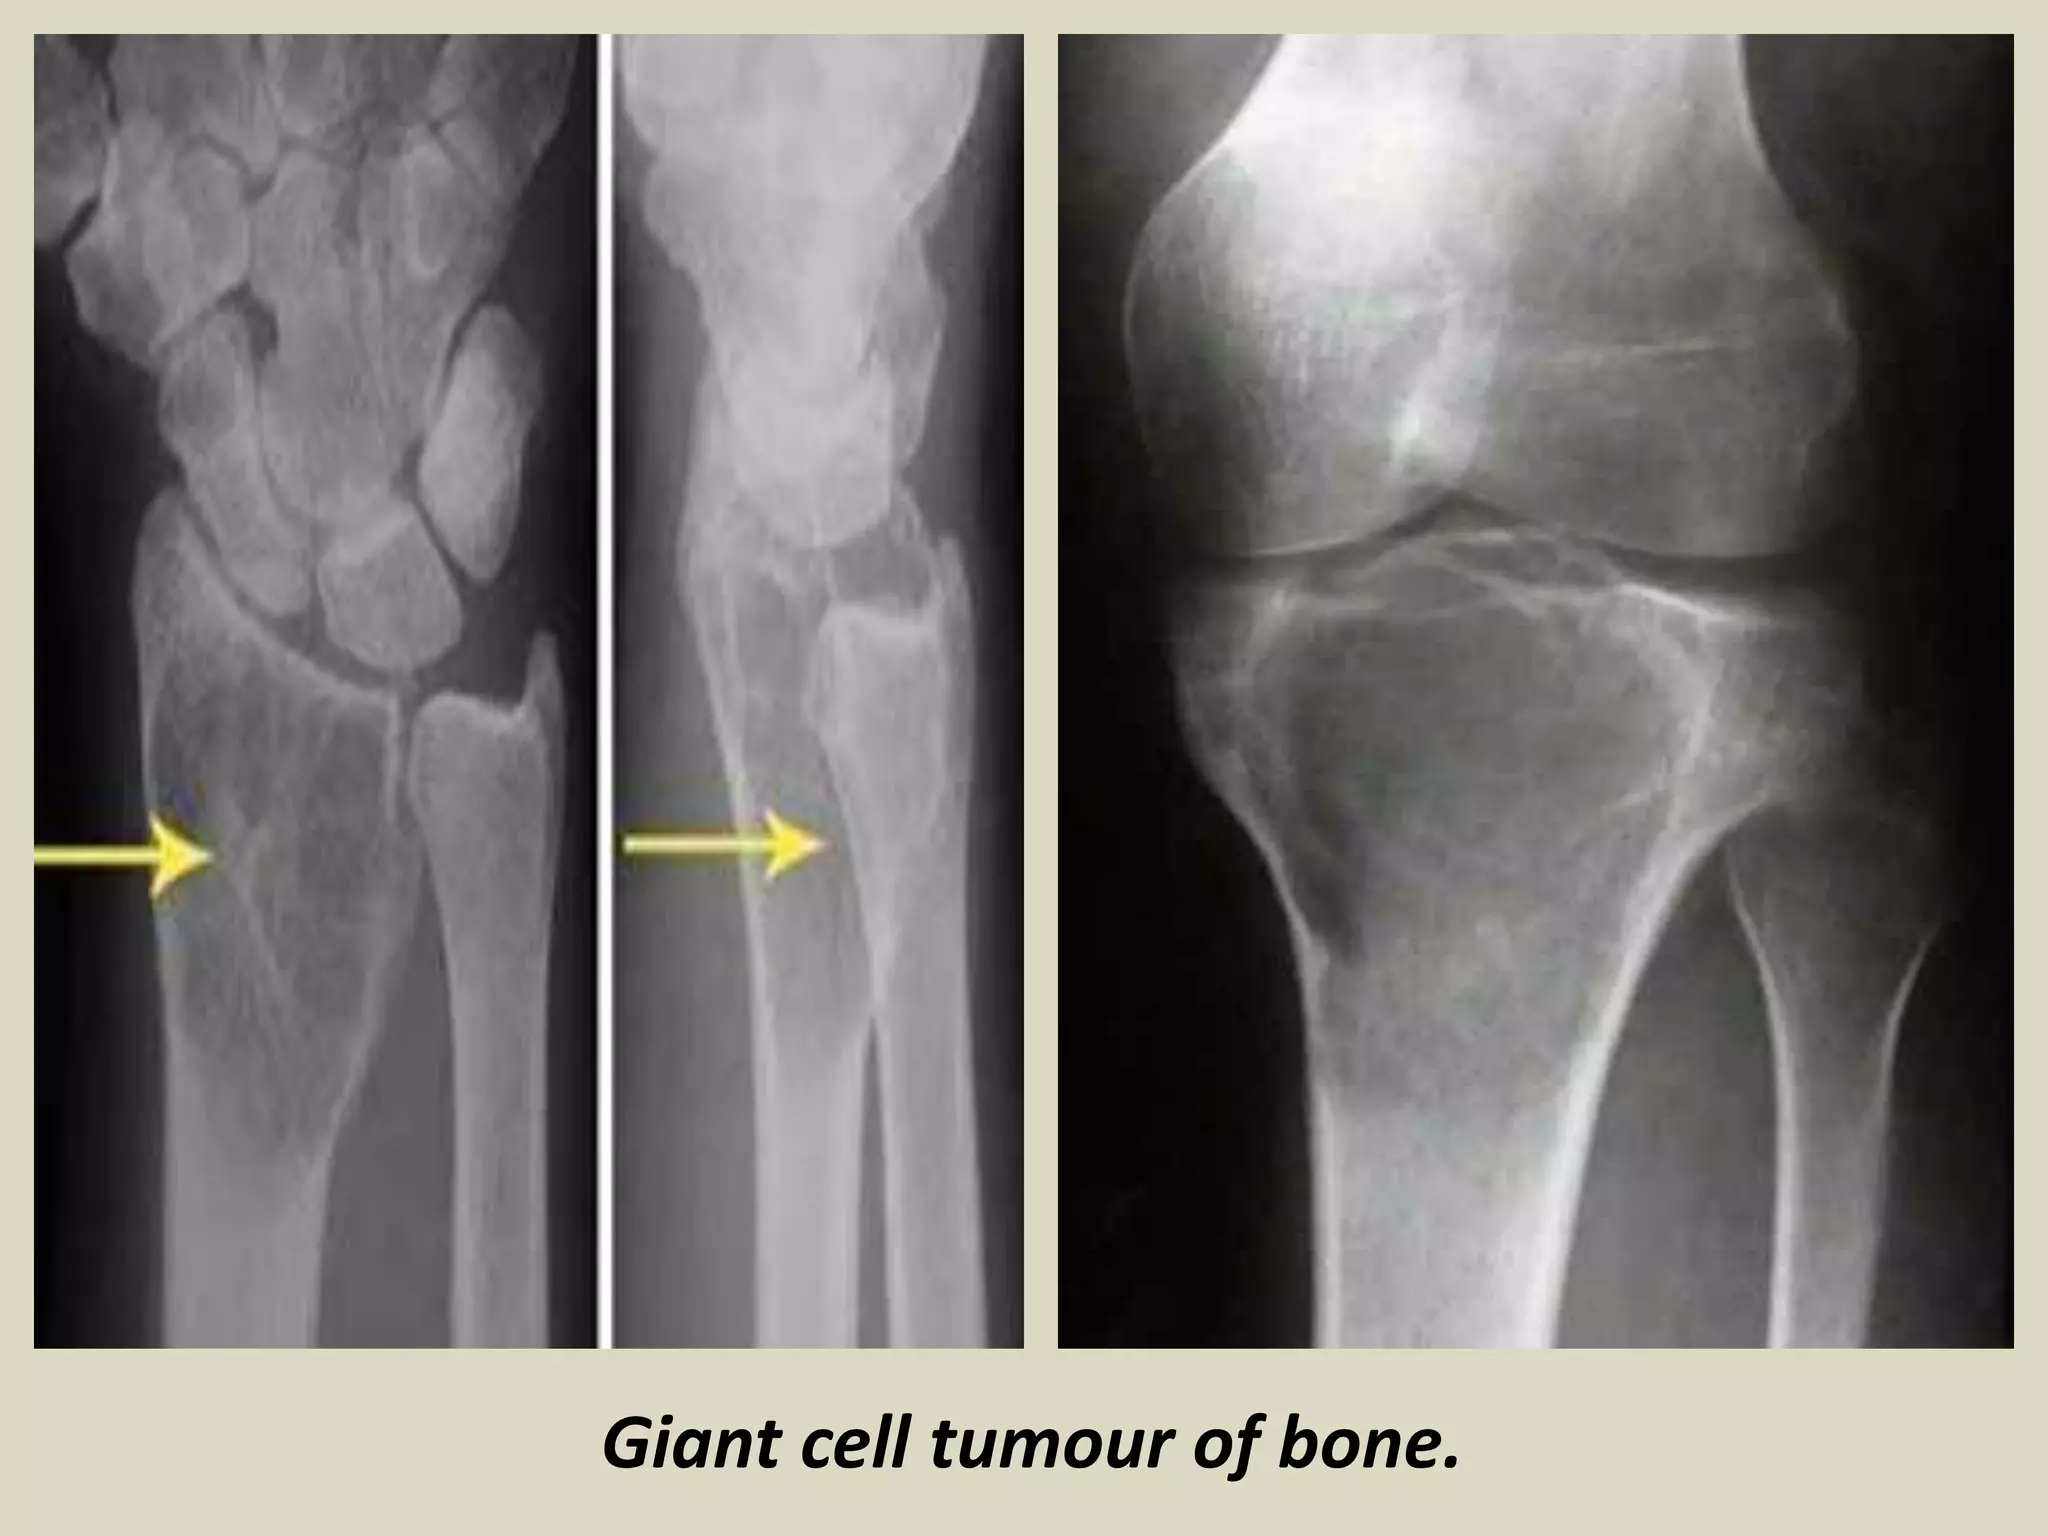

GIANT CELL TUMOR

Definition: Benign, locally aggressive neoplasm.

- Composed of sheets of neoplastic ovoid mononuclear cells interspersed with

uniformly distributed large, osteoclast like giant cells.

Epidemiology:

- Giant cell tumour represents around 4-5% of all primary bone tumours.

- Peak incidence is between the ages of 20 and 45.

- 10-15% of cases occur in the second decade.

- Not commonly seen in adolescents, although cases were described.

- There is slight female predominance described.

Sites of involvement:

- Giant cell tumours typically affect the ends of long bones, especially the distal femur, proximal tibia, distal

radius and proximal humerus.

- About 5% affect flat bones, especially those of the pelvis.

- Multicenteric giant cell tumors are very rare and tend to involve the small bones of the distal extremities.

Clinical findings:

- Patients typically present with pain, swelling and often limitation of joint movement

- Pathological fracture is seen in 5-10% of patients.

Imaging:

- X-rays of lesions in long bones usually show an expanding and eccentric area of lysis.

- Lesion normally involves the epiphysis and adjacent metaphysis.

- Extension up to the subchondral plate, sometimes with joint involvement may be present.

- Rarely, the tumour is confined to the metaphysis, usually in adolescents where the tumour lies in relation

to an open growth plate, but occasionally also in older adults.

- Diaphyseal lesions are exceptional.

- CT scanning gives a more accurate assessment of cortical thinning and penetration than plain radiographs.

Giant cell tumour of bone.